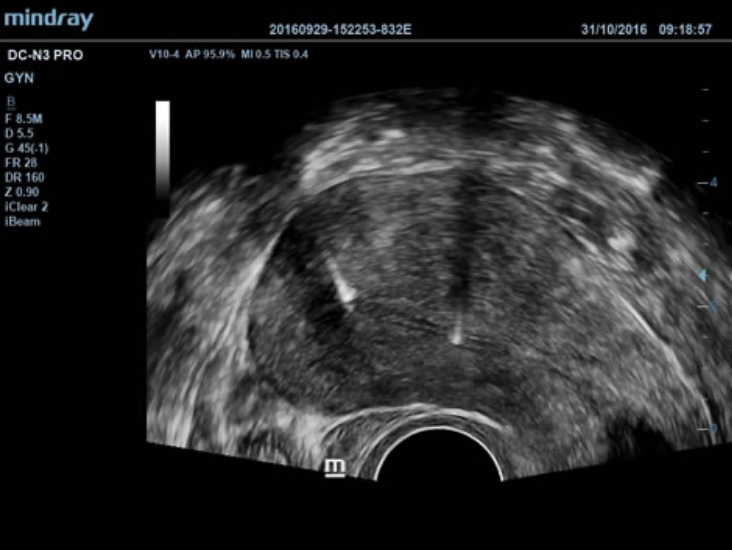

DC-N3 PRO? ??? ??? ??, ???, ???? ?? ???? ??? ?? ?????. ?? ??? DC-N3 PRO? ??? ??? ?? ??? ??? ???? ???? ??? ????? ??????. ???? ?? ???? ???? ?? ??? ???? ???? ???? ?? ? ????.

DC-N3 PRO? ??? ??? ?? ??? ??? ????? ?? ???? ???? ??? ?? ??? ??? ?? ???? ??? ?????. ?? ??? ??, ???, ??? ?? ??? ??? ??? ?????. ????? ???? ???? ????? ??? ???? ??? ?? ?? ?? ??? ??? ???? ??? ?????.